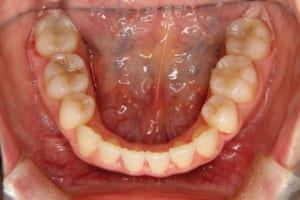

治療前

主訴 下の歯の凸凹

上の前歯が出ているのが気になる

その他/備考 上顎右側中切歯および側切歯が、埋伏していた犬歯によって歯根吸収していました。